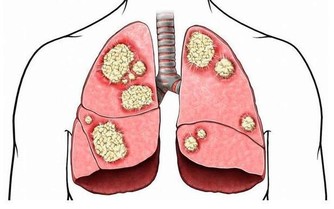

5、補點魚油

醫生發現,多吃魚有助於緩解類風濕關節炎病情。其原因是魚肉中的歐米伽3脂肪酸具有緩解體內炎症的作用。